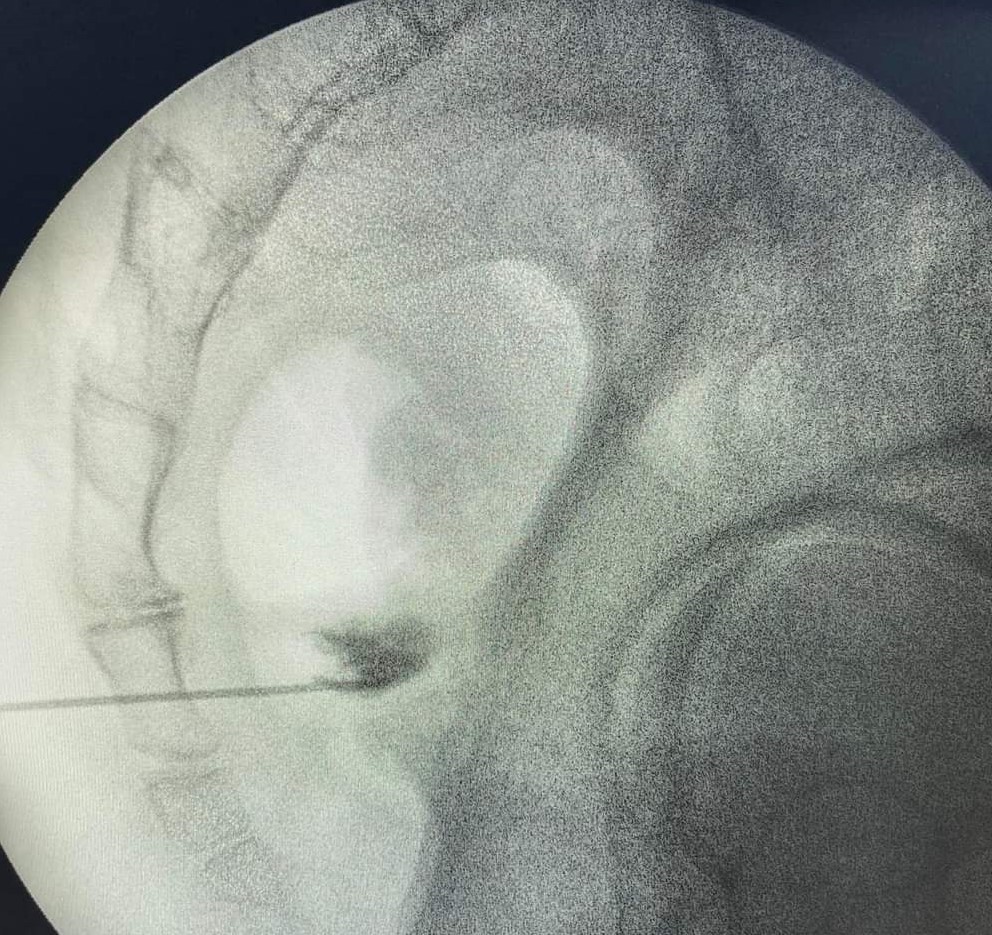

- Νευρόλυση με χρήση παλμικής ραδιοσυχνότητας υπό ακτινοσκοπική καθοδήγηση

- Φαρμακευτικό block με στεροειδή και τοπικό αναισθητικό